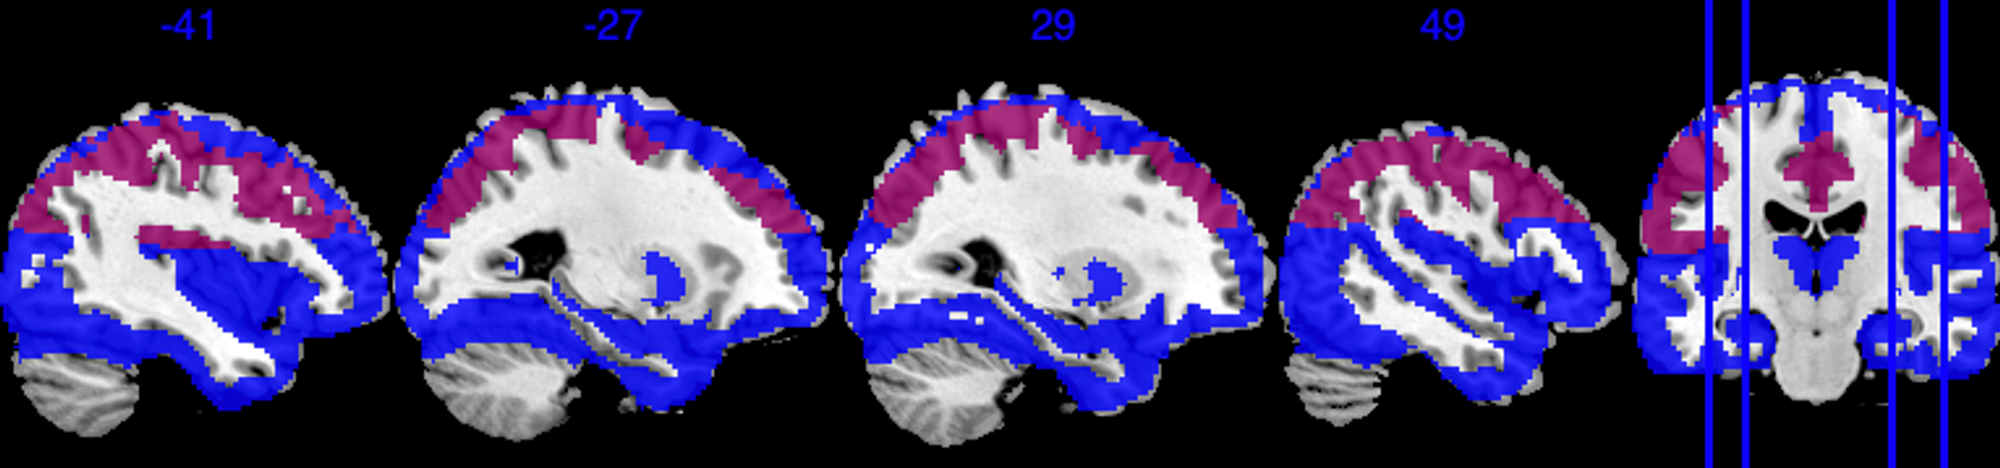

To define the analysis mask, we recall the definition of observed proportion (OP) at location to be , where is the set of all observed locations for individual . We define the group analysis mask as , i.e., the area where each voxel has at least 50% observed data. As shown in Figure 2, the group analysis mask with completely observed data (purple area) covers significantly less area compared to , which has at least 0.5 observed proportion (blue area). In the complete observed data, large portions of the brain regions are missing, notably including the orbitofrontal cortex, the inferior temporal cortex, and the amygdala—regions crucial for emotion processing. In particular, the mask with complete observed data contains only 52 out of the 110 regions in the Harvard-Oxford atlas.

After applying a common mask with an observed proportion of 0.5, we end up with that contains voxels. The image outcomes are standardized across subjects, i.e. where is the original image for subject location , is the sample mean, and SD[M(s)] is the standard deviation of . For each region, we apply the Matérn kernel function but with different and parameters (6), to account for the different smoothness of each region. Both and are determined through grid search so that the empirical covariance of and the estimated covariance by the Matérn kernel have the smallest difference in Frobenius norm. The number of bases is chosen so that the cumulative summation accounts for 90% of the total summation of all eigenvalues, hence we have a total number of . In Section 4.4.1, we provide a sensitivity analysis when the cutoff is based on 92% of the total summation.